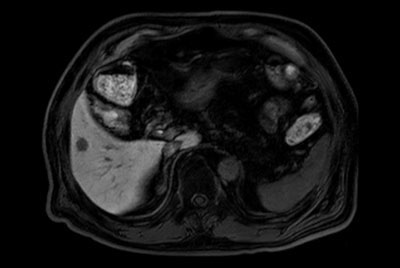

Liver metastasis – Free breathing